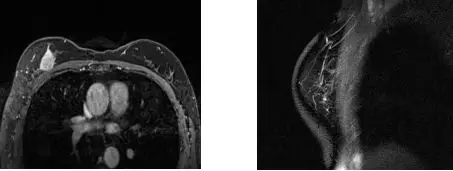

2015-6-22乳腺MRI示:右乳上方占位NAC 8周期后,肿块较前明显缩小,几近消失,BI-RADS 6。依据RECIST 标准评价,PR。

术后病理:(右乳改良根治标本)浸润性导管癌,分级无法评估。显微镜下纤维化间质内可见2灶浸润病灶,最大径分别为0.12cm和0.2cm。浸润性癌总体累及范围最大径0.8cm。腋窝淋巴结未见癌转移:(0/24)。其中阴性伴化疗反应淋巴结3枚;阴性无化疗反应淋巴结21枚。免疫组化:ER(-),PR(-),Her-2(-)